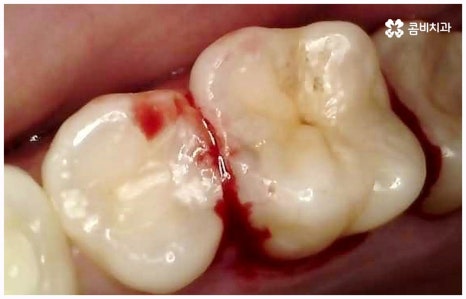

임플란트 종류 는 환자분들의 상황에 따라 달라지기 때문에 먼저 꼼꼼하게 정밀 검진을 받아보고 숙련된 의료진과 충분히 상담을 해 볼 필요가 있습니다. 환자분들의 치아 및 잇몸과 뼈의 상태, 전신 건강 등을 종합적으로 살펴보고 만약 필요하다면 선행 치료부터 받게 될 거예요. 선행 치료는 보통 임플란트 식립을 하게 된 치아 상실의 원인, 그리고 치아가 상실된지 얼마나 오랜 시간이 흘렀는지 여부에 따라 달라지는데 예를 들어 비교적 어린 나이에 큰 사고를 당해서 치아를 잃게 되었을 때 지체없이 바로 치과로 내원한 경우, 잇몸뼈가 건강하고 나이 등 회복력에 대한 기대치도 높은 편이며 다른 전신 질환, 상용약 등 잇몸에 지속적인 영향을 줄 만한 요소가 없다고 한다면 별다른 선행치료 없이 임플란트 종류 중 당일 심고 바로 임시 치아로 식사를 할 수 있는 원데이 임플란트를 통해 보다 빠르고 간편한 수복을 할 수 있어요.

보통은 인공 치근을 식립한 후에 얼마 동안 시간을 두어 골유착이 잘 일어나게 한 후에 지대주(연결 부위)를 연결하고 크라운 보철물을 제작, 장착해 주는데 여기서 개개인의 상황이 모두 다르기 때문에 회복 기간이 얼마나 걸릴지 정확하게 알 수는 없지만 대부분 3~6개월 정도라고 보면 될 거예요. 그동안은 불편한 상태로 사용을 할 수 밖에 없는데 만약 검진 및 발치, 식립, 임시 치아 제작 및 장착까지 모두 하루 만에 이루어진다면 임플란트 치료 기간을 줄일 수 있을 뿐 아니라 내원 횟수 및 통증과 불편감 또한 감소시킬 수 있을 것이기 때문에 시간적인 여유가 많지 않은 직장인분들, 학생들, 유학생분들이나 지방에 거주하시는 분들과 같은 경우에 임플란트 종류 중 원데이 임플란트 식립에 대해서 관심을 많이 보이고 있습니다. 그러나 말씀드린 것처럼 누구나 받을 수 있는 것은 아니기 때문에 먼저 잇몸뼈의 상태를 꼼꼼하게 체크하여 가능성 여부를 알아볼 필요가 있으니 검진 및 상담부터 진행해 보시길 권유드리고 있어요.